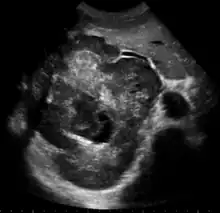

Upon discovery of a liver tumor, the main issue in the workup is to determine whether the tumor is benign or malignant. Many imaging modalities are used to aid in the diagnosis of malignant liver tumors. These include sonography (ultrasound), computed tomography (CT) and magnetic resonance imaging (MRI).

Ultrasonography of liver tumors involves two stages: detection and characterization. Tumor detection is based on the performance of the method and should include morphometric information (three axes dimensions, volume) and topographic information (number, location specifying liver segment and lobe/lobes). The specification of these data is important for staging liver tumors and prognosis. Tumor characterization is a complex process based on a sum of criteria leading towards tumor nature definition. Often, other diagnostic procedures, especially interventional ones are no longer necessary. Tumor characterization using the ultrasound method will be based on the following elements: consistency (solid, liquid, mixed), echogenicity, structure appearance (homogeneous or heterogeneous), delineation from adjacent liver parenchyma (capsular, imprecise), elasticity, posterior acoustic enhancement effect, the relation with neighboring organs or structures (displacement, invasion), vasculature (presence and characteristics on Doppler ultrasonography and contrast-enhanced ultrasound (CEUS).